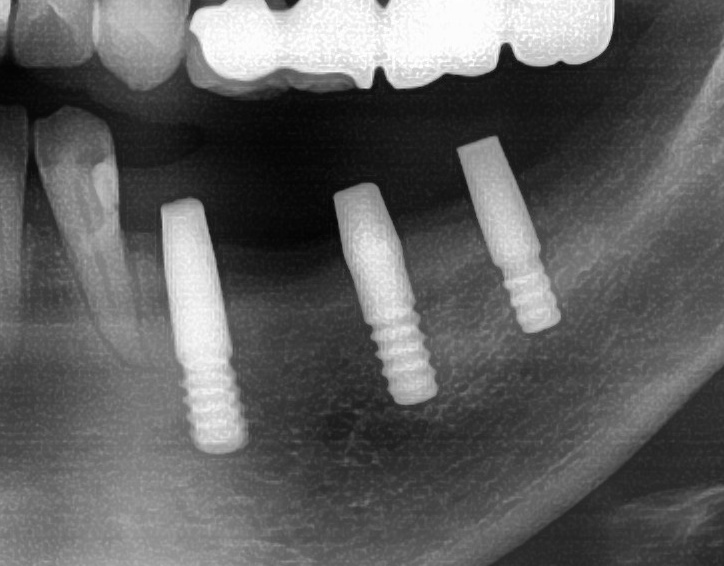

今回の患者様はインプラント植立を希望され、左下4番目・5番目・6番目の3本の植立が決まりました。

開けた穴に、専用道具を使ってネジを締めるように長さ2センチ程のインプラントを骨に埋め込んでいきます。

続けて他の歯も同じように植立していきます。

インプラントオペでは、複数本を植立する場合でも、当時進行はせず、1本ずつ同じ工程を繰り返して植立します。

しっかりとインプラント埋め込まれた後は、動揺がないか、噛んだ時に当たらないかなどを確認して、最後にパノラマ写真を撮影して今回のオペは終了となりました。